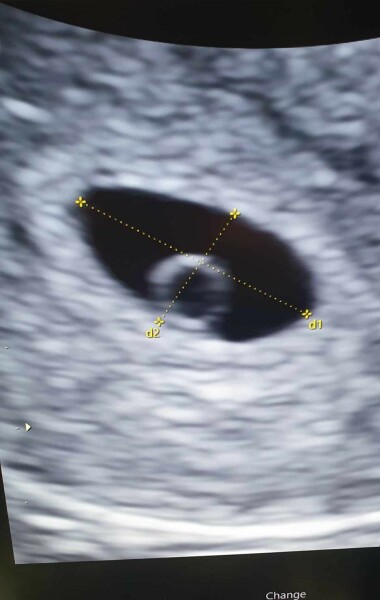

So i had my early ressurance scan today, The baby is in the right position and my date is correct 5 weeks 5 days today. We saw egg sac and gestation sac, and could also see that I ovulated from my left side wich confirms the pain I had 12/13 March when flo predicted my ovulation was wondering if I was feeling ovulation pain and seems I'm intuned with my body lol

Going back for my second scan 24th April where I will be 8 weeks to hopefully see fetal pole and heartbeat